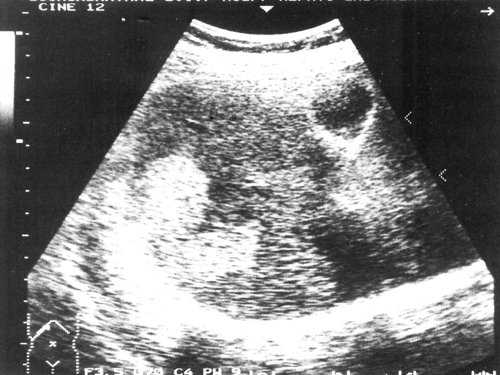

Гемангиомы печени часто оказываются случайной находкой при ультразвуковом обследовании. Им свойственна характерная эхогенность, четкие признаки. Обычно диагноз может быть заподозрен при первом обследовании. Гемангиома имеет широкий спектр признаков при УЗ-обследовании. Наиболее общими, признаваемыми "типичными" признаками являются - маленький размер (диаметр не более 4 см), равномерное повышение эхогенности внутренней структуры, четкие контуры, субкапсулярное расположение в правой доле печени [9,10]. Нередко за гемангиомой наблюдается усиление звука [11]. Последующее наблюдение редко выявляет изменения в размере [7].

Небольшие гемангиомы обычно состоят из больших наполненных кровью кавернозных полостей, ограниченных слоем плоскоклеточного эпителия и разделенных фиброзными перегородками [12]. При микроскопии образование имеет ячеистую структуру. Множественные перегородки внутри гемангиомы создают характерную гиперэхогенность структуры [7]. Однако по мере роста гемангиомы могут произойти различные изменения: внутреннее кровотечение с некрозом, миксоматозные изменения, тромбоз, фиброз, кальцификация [13]. Эти изменения при эхографии могут проявляться гипоэхогенными, смешанной эхогенности и анэхогенными участками. Более того, исследование гемангиом размером более 4 см в диаметре показало, что некоторые из них имеют дольчатый контур, который соотвествует капсуле, определяемой при гистологическом исследовании и являющейся стенкой опухоли [5].

При наличии диффузной жировой инфильтрации гемангиому сложнее обнаружить при ультразвуковом исследовании [14]. Возросшая эхогенность печеночной паренхимы, инфильтрированной жиром, маскирует гемангиому. В случаях минимально выраженной жировой инфильтрации повреждения эхо-структуры могут быть минимальными, либо отсутствовать. В более выраженных случаях определяется зона повышенной эхогенности. Ультразвуковая картина гемангиомы печени при жировой инфильтрации будет меняться следующим образом - от гиперэхогенной вначале до изоэхогеннои и далее гипоэхогеннои по сравнению с инфильтрированной печенью.